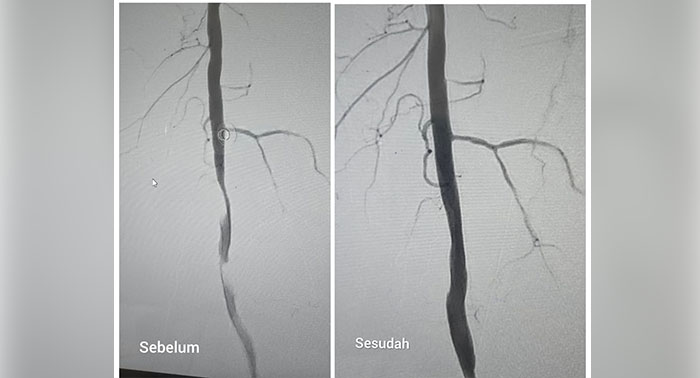

RSUD Blambangan Berhasil Lakukan Tindakan Medis untuk Membuka Penyempitan Pembuluh Darah Arteri (Foto: RSUD Blambangan/BWI24Jam)

BWI24JAM.CO.ID, Banyuwangi - RSUD Blambangan kembali mencatat prestasi di bidang layanan kesehatan. Untuk pertama kalinya, rumah sakit milik Pemkab Banyuwangi itu sukses melakukan prosedur angioplasti perifer, tindakan medis intervensi vaskular untuk membuka penyempitan pembuluh darah arteri pada kaki pasien.

Prosedur ini dilakukan tim dokter dengan teknik minim invasif, menggunakan kateter dan balon khusus yang dimasukkan melalui lipatan paha pasien. Tindakan tersebut hanya memerlukan sayatan kecil tanpa operasi terbuka.

“Dengan tindakan ini, aliran darah yang sebelumnya tersumbat bisa kembali lancar tanpa perlu operasi besar,” kata dr Nizam Fahmi Sp.Rad, Subsp. RI (K), dokter radiologi konsultan RSUD Blambangan yang memimpin prosedur tersebut, Senin (20/10/2025).